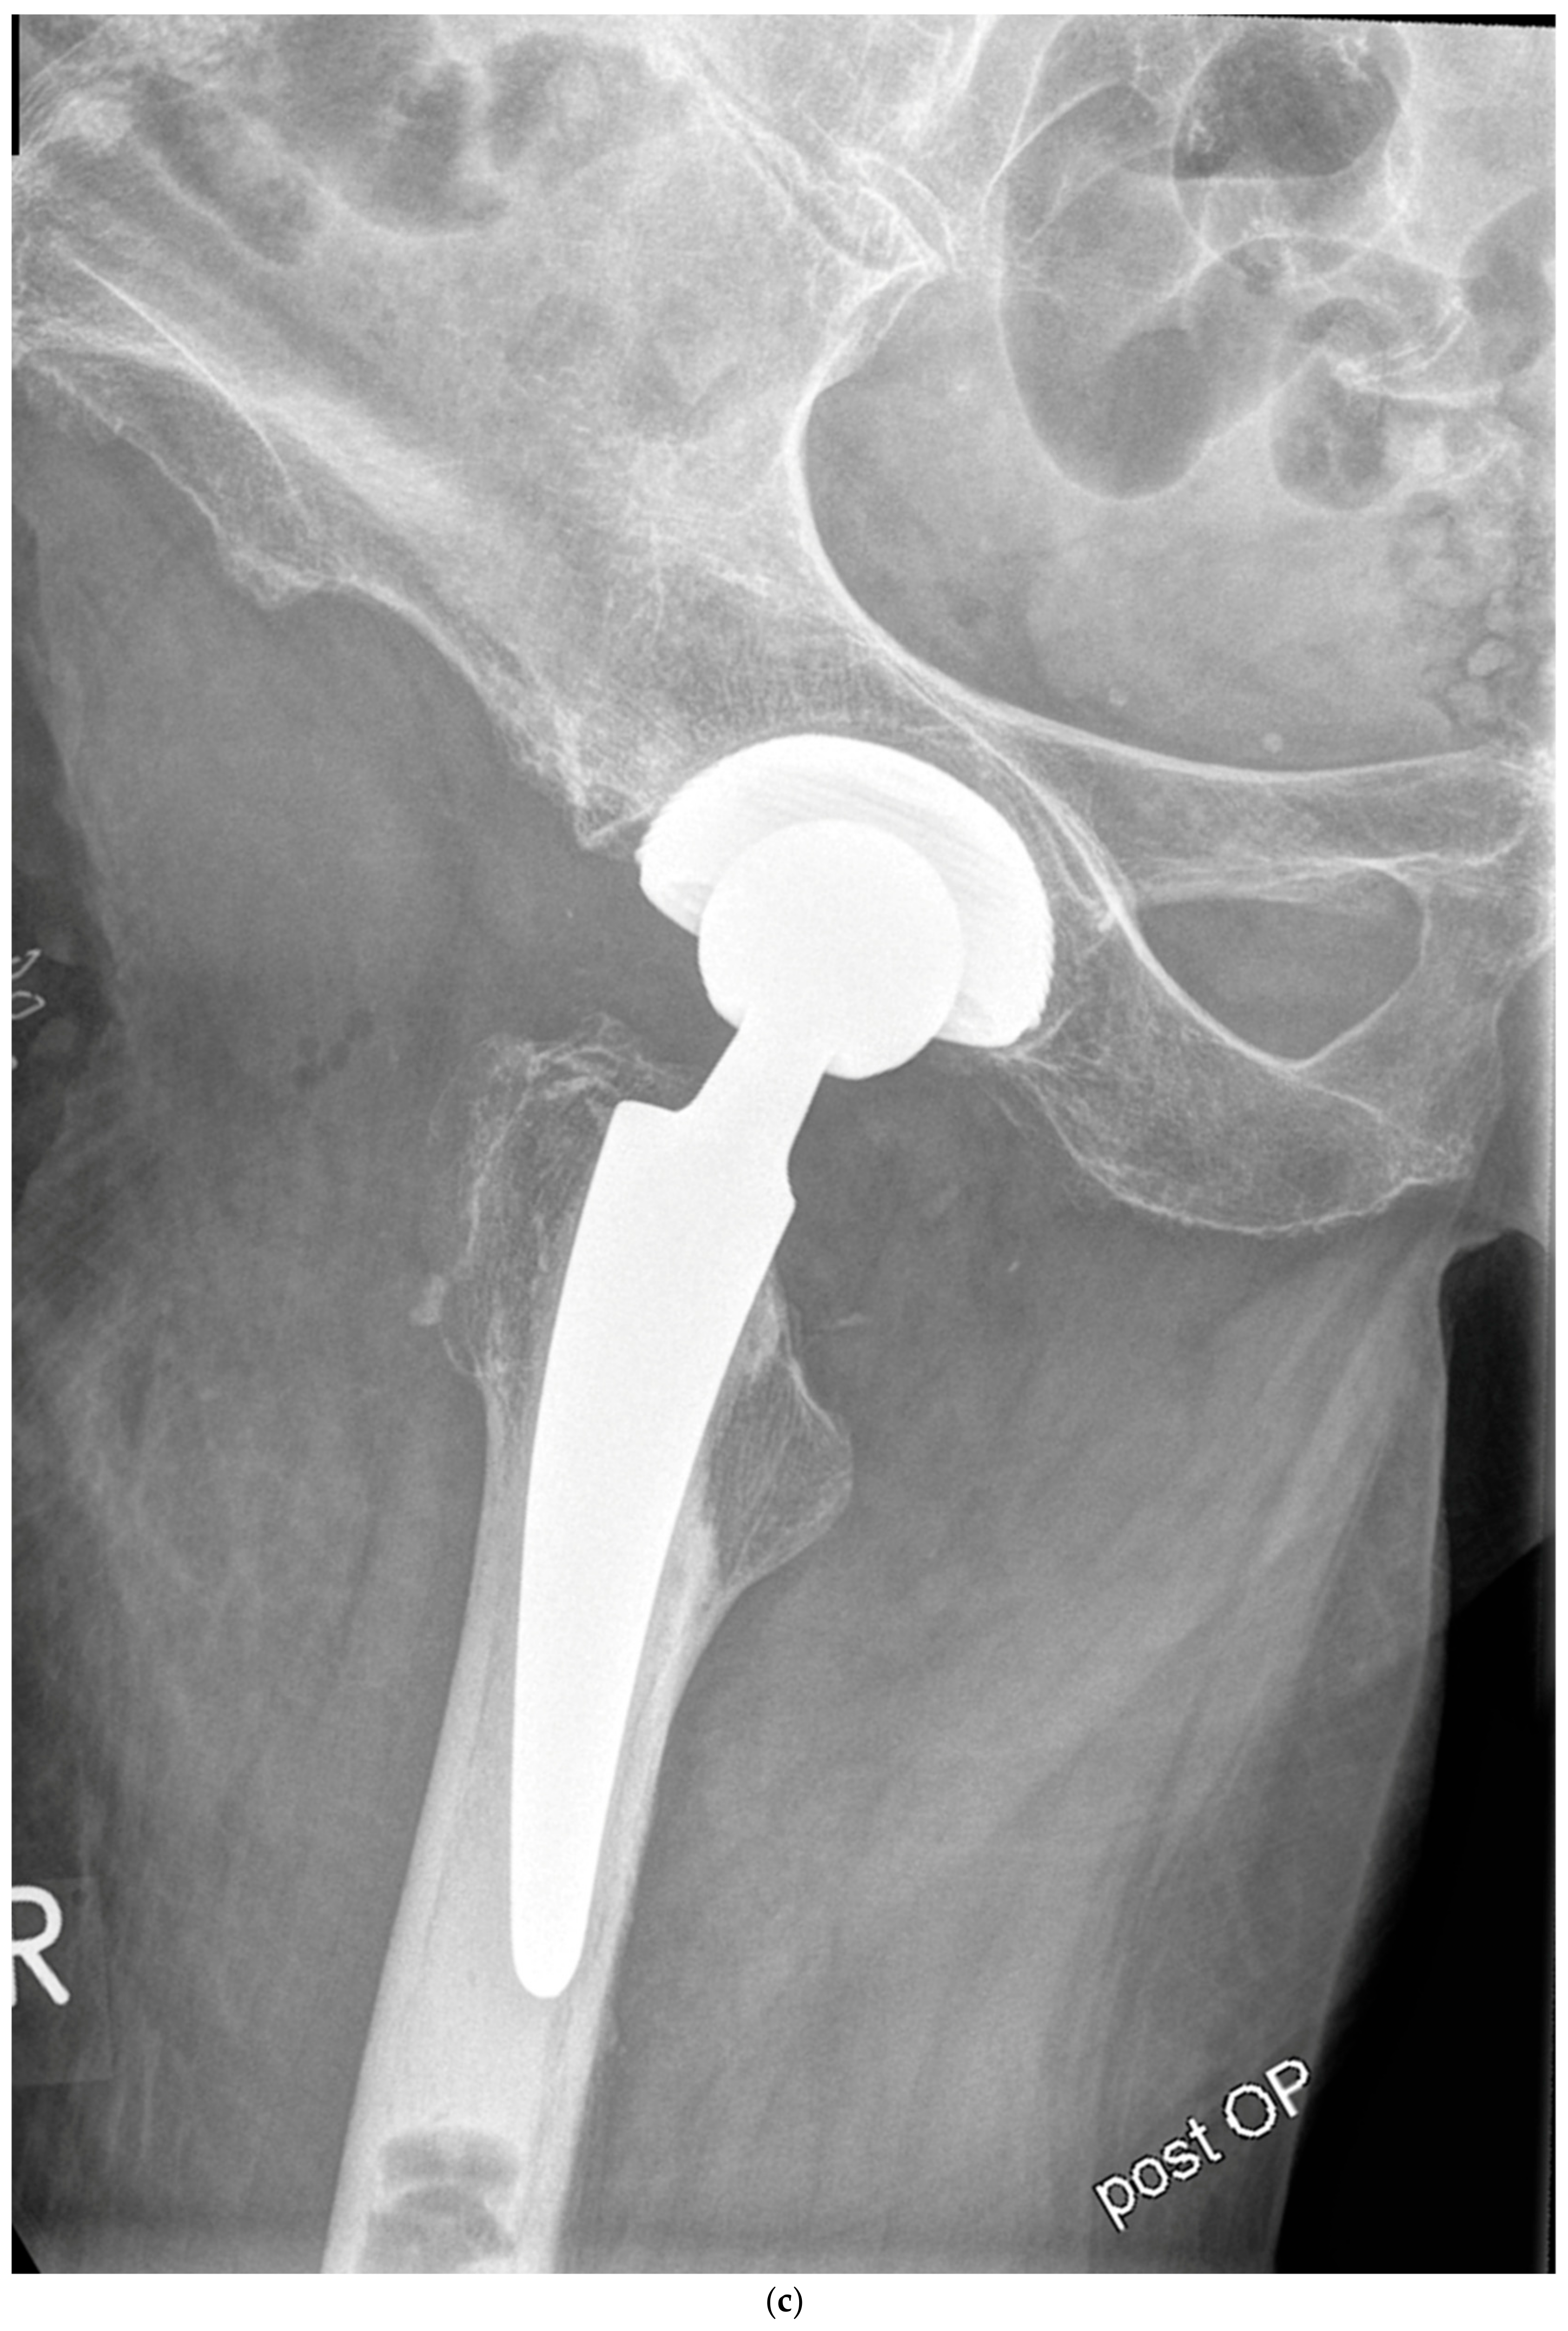

2. Materials and Methods